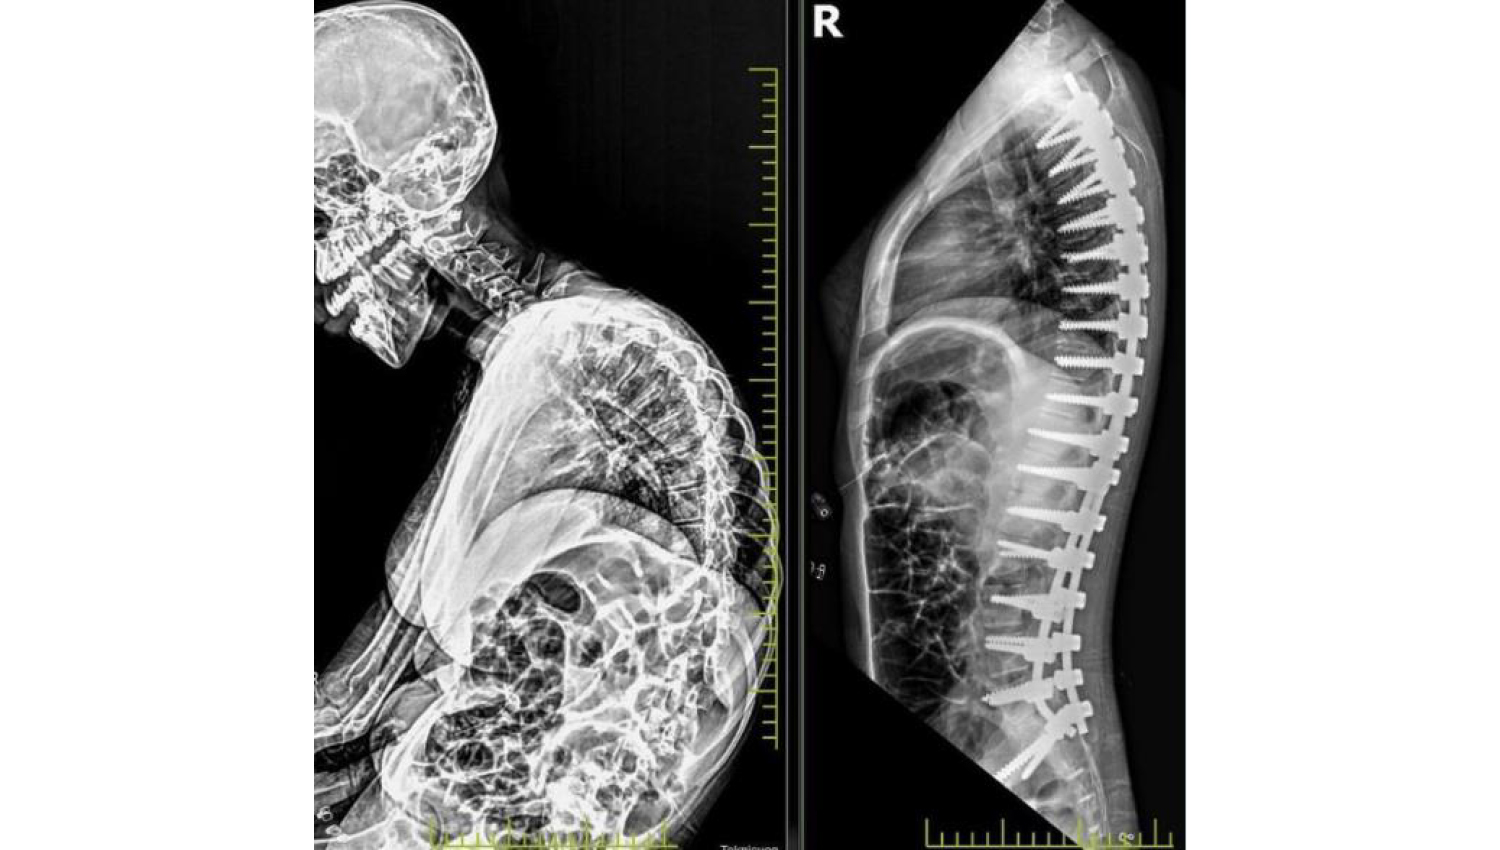

1.Initial radiological view.

2.Metrosan-Ligamed Posterior Polyaxial Spine Stabilization Screws, Titania Polyaxial Reduction Screw, Titanium Rod and Powerbone Flexible Greft products were used with surgical intervention to treat scoliosis.

3.Post-operation radiological view.